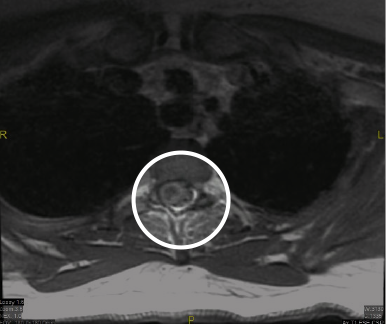

The MRI demonstrated expansion of the spinal cord, starting at C5 and extending to the T9–T10 level (see Figure 1). The MRI showed areas of hemorrhage in the spinal cord most prominent at the T2 level, with multiple serpentine structures consistent with a spinal cord vascular malformation (sAVM) (see Figure 2). The cord edema and expansion presumably reflected venous congestion/hypertension (see Figure 3). A neurosurgery consultation was obtained, and a catheter angiography was performed, localizing the lesion. At the choice of the patient and her family, the patient elected to transfer to another hospital.

Figure 2: Thoracic MRI showing areas of hemorrhage in the spinal cord most prominent at the T2–T3 level, with multiple serpentine structures, most in keeping with a spinal cord vascular malformation such as an sAVM.

Figure 3: Thoracic MRI expressing cord edema and expansion, presumably reflecting venous congestion/hypertension. The cord appears to be scalloped due to dilated perivascular vessels.